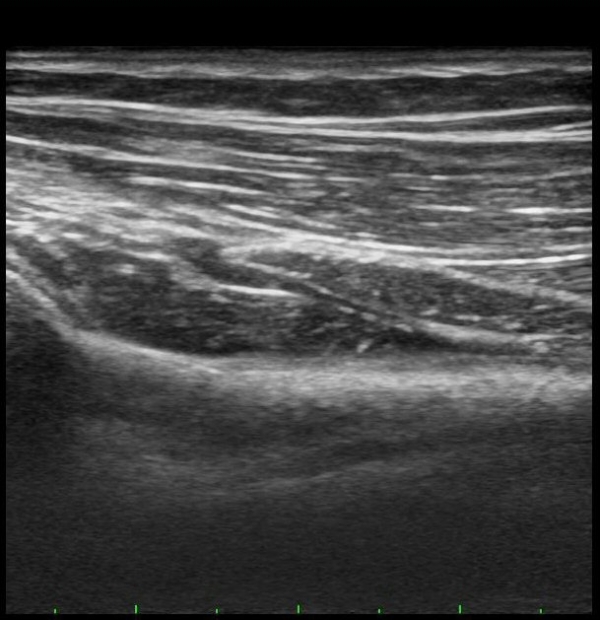

ÆÈ²ÞÄ¡ ¾ÕÂÊ È¾´Ü¸é°Ë»ç¿¡¼­ Èİñ°£½Å°æ(PIN)ÀÌ ¿ä°ñµÎ Àü¹æ¿¡¼­  Á¤»óÀûÀ¸·Î °üÂûµÊ(±×¸² 1).